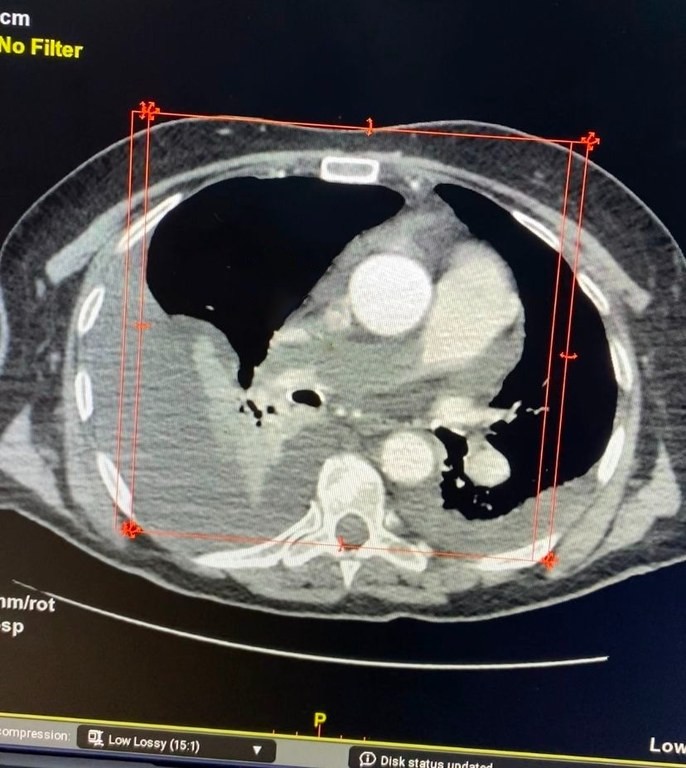

Uma paciente de 81 anos foi submetida à retirada de um trombo maciço (coágulos que obstruem as artérias do pulmão) dentro do principal vaso do pulmão, em um procedimento chamado de trombectomia mecânica. A cirurgia foi feita com sucesso, por meio da infiltração de um fármaco trombolítico (medicamento para desmanchar trombo ou coágulos) diretamente nos vasos pulmonares, de forma a digerir os trombos residuais.

De acordo com o médico hemodinamicista Jeann Santiago, responsável pelo procedimento, a trombectomia (remoção de um coágulo sanguíneo – trombo – de um vaso sanguíneo) foi crucial para a vida da paciente. “Caso não tivesse sido feito o diagnóstico e o tratamento invasivo na hemodinâmica, inevitavelmente teríamos um desfecho ruim devido à gravidade da situação”, disse.

A paciente evoluiu bem após o procedimento e, nesta quarta-feira (17), já apresentava saturação de oxigênio de 96%, dentro da normalidade. No dia em que ela deu entrada na sala de cirurgia, estava com apenas 72% de saturação. Ainda nesta quarta-feira a idosa deve ter alta para a enfermaria.